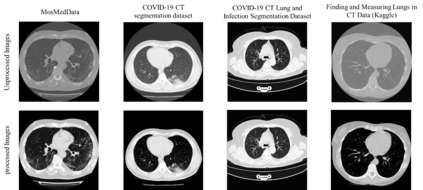

Since the breakout of coronavirus disease (COVID-19), the computer-aided diagnosis has become a necessity to prevent the spread of the virus. Detecting COVID-19 at an early stage is essential to reduce the mortality risk of the patients. In this study, a cascaded system is proposed to segment the lung, detect, localize, and quantify COVID-19 infections from computed tomography (CT) images Furthermore, the system classifies the severity of COVID-19 as mild, moderate, severe, or critical based on the percentage of infected lungs. An extensive set of experiments were performed using state-of-the-art deep Encoder-Decoder Convolutional Neural Networks (ED-CNNs), UNet, and Feature Pyramid Network (FPN), with different backbone (encoder) structures using the variants of DenseNet and ResNet. The conducted experiments showed the best performance for lung region segmentation with Dice Similarity Coefficient (DSC) of 97.19% and Intersection over Union (IoU) of 95.10% using U-Net model with the DenseNet 161 encoder. Furthermore, the proposed system achieved an elegant performance for COVID-19 infection segmentation with a DSC of 94.13% and IoU of 91.85% using the FPN model with the DenseNet201 encoder. The achieved performance is significantly superior to previous methods for COVID-19 lesion localization. Besides, the proposed system can reliably localize infection of various shapes and sizes, especially small infection regions, which are rarely considered in recent studies. Moreover, the proposed system achieved high COVID-19 detection performance with 99.64% sensitivity and 98.72% specificity. Finally, the system was able to discriminate between different severity levels of COVID-19 infection over a dataset of 1,110 subjects with sensitivity values of 98.3%, 71.2%, 77.8%, and 100% for mild, moderate, severe, and critical infections, respectively.